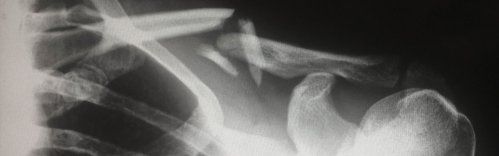

Ofrecemos atención especializada y personalizada para tu recuperación tras lesiones por accidentes de tráfico, con un equipo experto en traumatología y cirugía ortopédica.[...]

Abordamos una amplia variedad de casos en el ámbito de la traumatología general. Te proporcionamos un enfoque completo en el tratamiento de una amplia gama de lesiones y condiciones.[...]